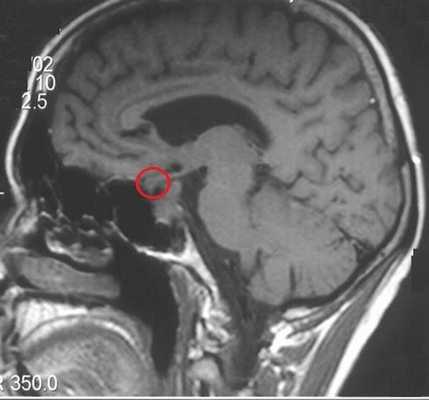

МРТ гипофиза до и после операции по удалению макроаденомы гипофиза